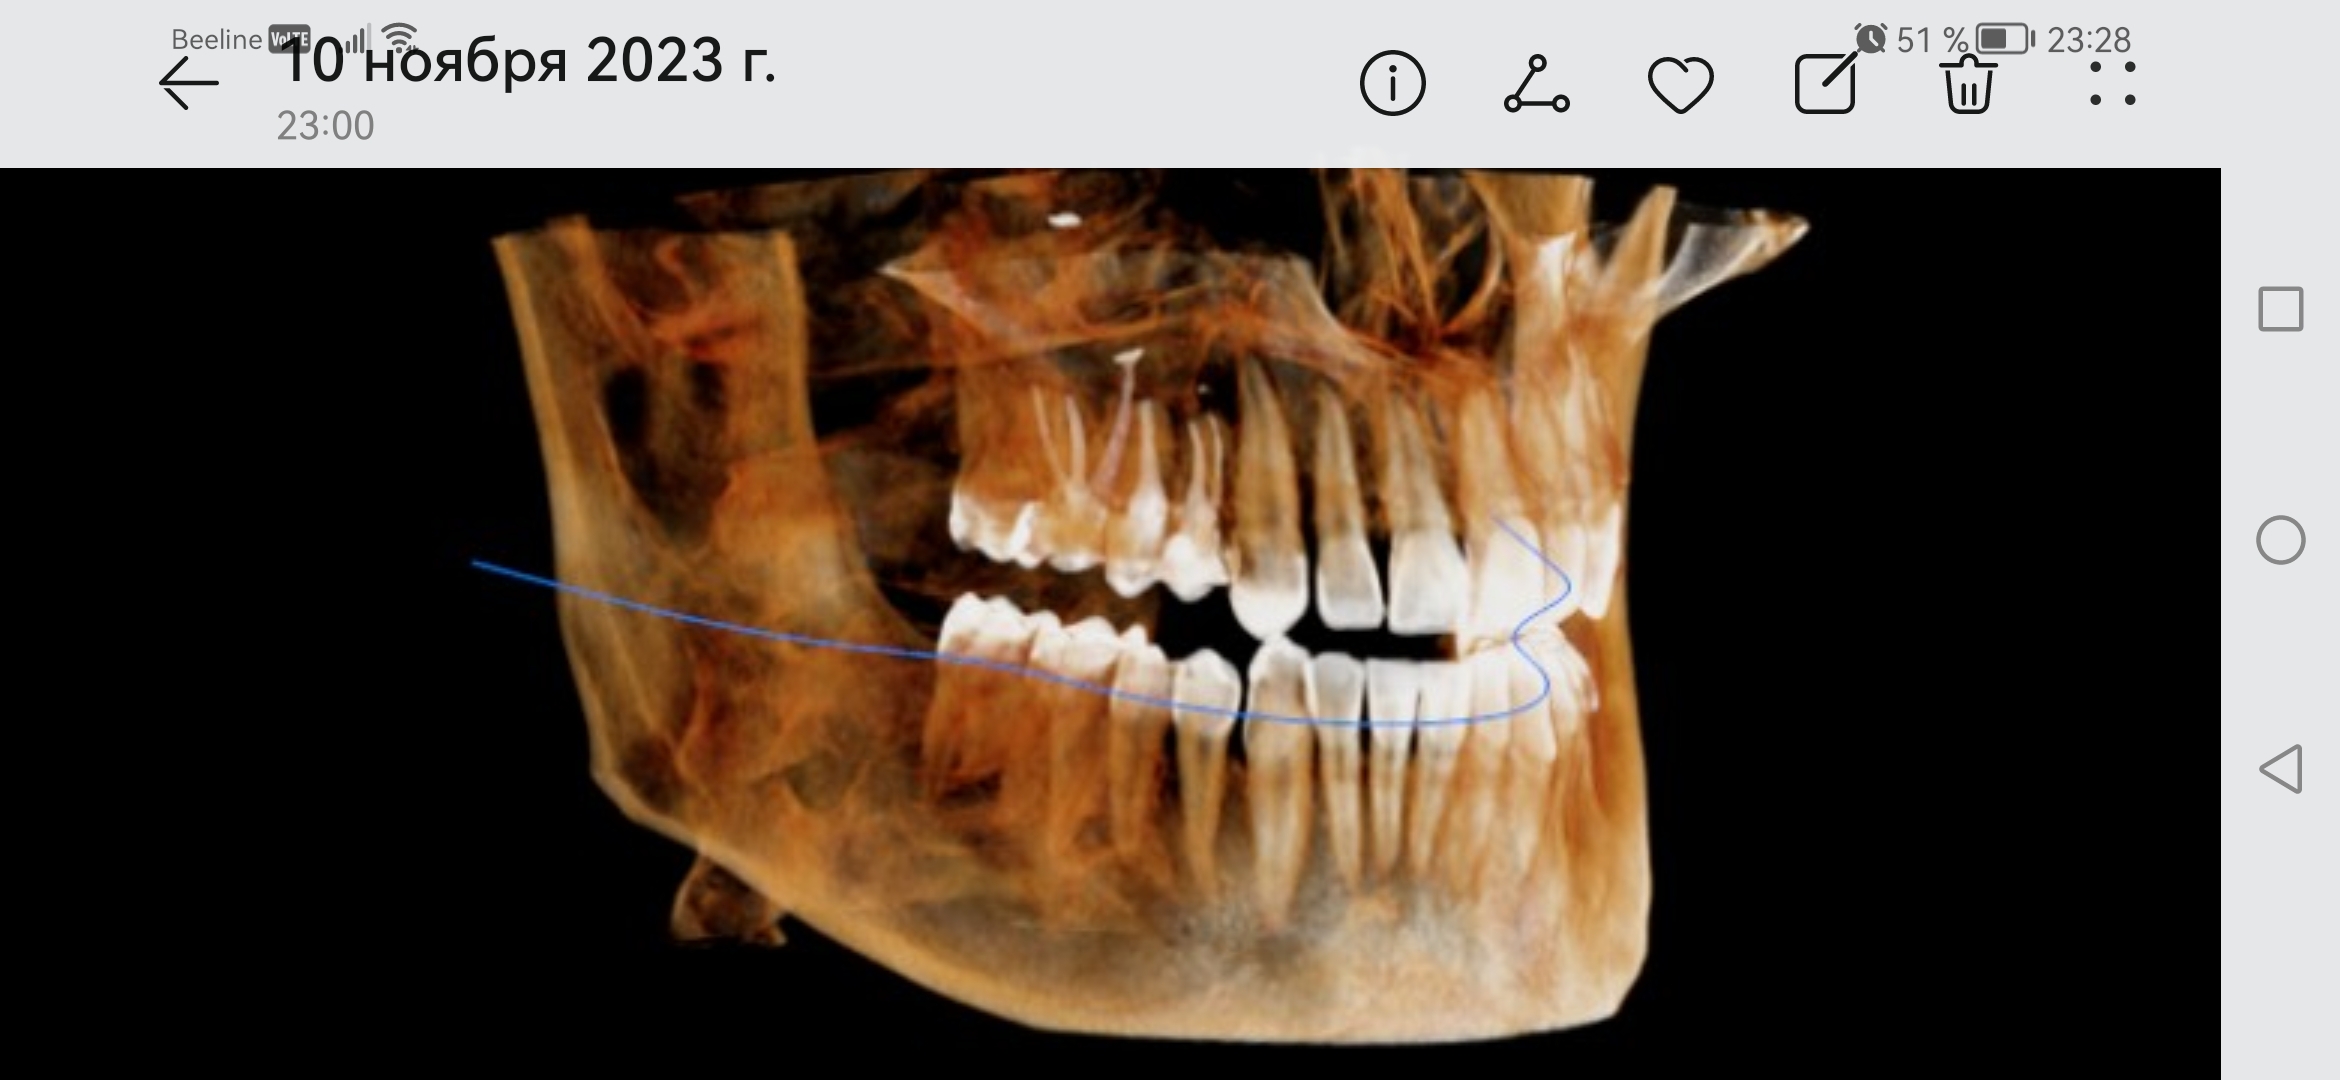

Screenshot20231[...].jpg 414Кб, 2340x1080

Screenshot20231[...].jpg 482Кб, 2340x1080

Боя, я в ахуе, вы в каком веке живёте. Есть такая штука как КЛКТ, стоит копейки, делается 2 минуты. Является золотым стандартном диагностики ЛЮБЫХ зубных пиздецом, там в 3д видно все - кисты, периодонтиты, состояние пазух и тд. Любой приличный врач а) не станет производить серьёзных манипуляций без таких снимков б) спокойно все увидит и распишется где и из за чего у вас болит. Нет бля ходят что-то лечат неизвестно что, не могут определить что и где у них болит, вы ебанутые?